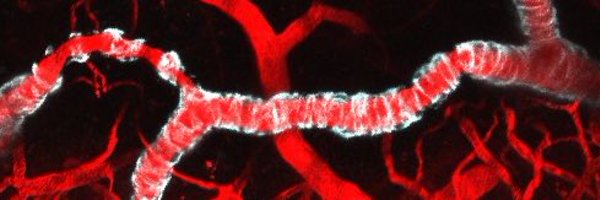

Using multi-modal imaging, Kozberg et al. report that loss of vasomotion occurs early in cerebral amyloid angiopathy in a mouse model. This loss coincided with initial vascular amyloid-β deposition and preceded the occurrence of microbleeds. Read at https://t.co/xljnepCErD

How does vascular dysfunction progress in #CAA? See our pre-print which used a combo of in-vivo two-photon microscopy and MRI to track changes in #vasomotion, #pulsatility, #CBF, #CVR, and more!

Background Cerebral amyloid angiopathy (CAA) is a cerebral small vessel disease in which amyloid-β accumulates in vessel walls. CAA is a leading cause of symptomatic lobar intracerebral hemorrhage...